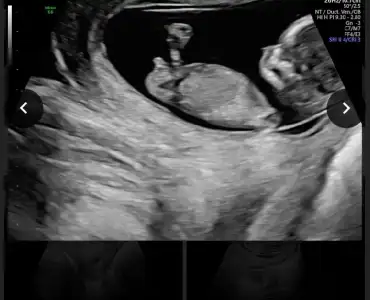

Karından baktı ise kız vajinal ise erkek en iyi 11 12 13 haftalar olmalı

karından ultrasın 9+4 :)

Ikra meyra cıgim.. bizim çıkıntı paralel gorunmuyor mu. Kız gibi olmasin sanki. Aslinda ben çikınti da goremedim de